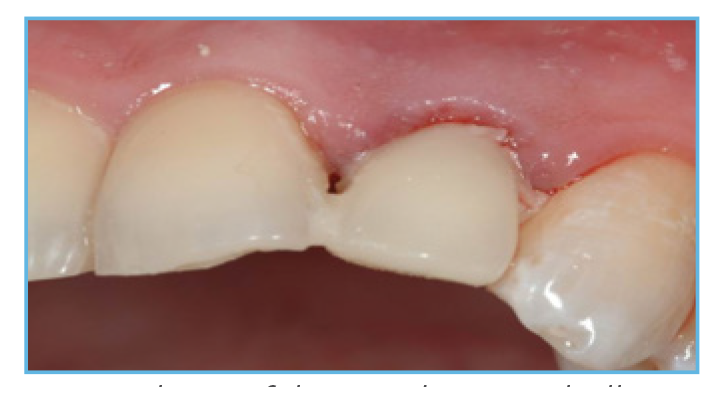

Fig. 1. NanoTite® Certain Implant in place. The bone was profiled around the interface.